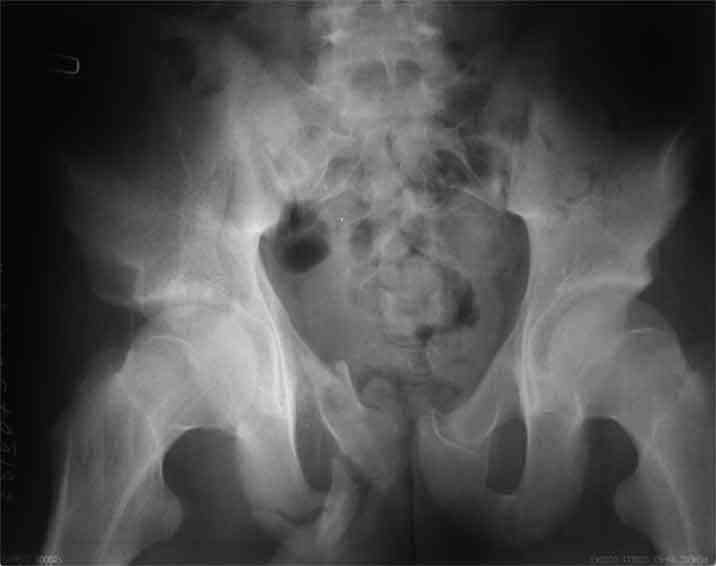

Поступил пациент, 16 лет, 1 мес после травмы.

Как вы считаете, надо ли оперировать вертлужную впадину? И как, кстати, классифицировать такое повреждение?

А чего там собственно таинственного? Билатеральное ротационно-нестабильное повреждение таза, перелом крестца в I зоне (по Denis)справа,частичное повреждение левого КПС, оскольчатые переломы лонной, седалищной костей справа (В3.2). Повреждение достаточно стабильное + молодой возраст+ сроки - оперативного лечения не требует.

По поводу классификации повреждения тазового кольца( по тем данным . что видны на представленных картинках):

по Pennal et al.- латеральное компрессионное повреждение тип В(ротационно-нестабильное (внутренняя ротация), вертикально стабильное)

по Tile classif. тип В2-1 - частично стабильное повреждение с неполным разрывом задней дуги.

По вертлуге- смог разглядеть только изолированный перелом передней колонны.

Насколько я понял из твоего письма, обращенного к анонимному vit, ты не видишь показаний к реконструкции перелома. Я бы взялся за реконструкцию(илео-ингвинальный доступ), хоть прошел и месяц после травмы: боковая 3Д показывает смещение нагрузочной зоны впадины, что однозначно будет способствовать разрушению хряща головки и впадины( особенно у 16 летнего пациента с ожидаемым высоким уровнем активности) + изменение геометрии впадины за счет неустраненного смещения фрагментов колонны (КТ, 3Д данные).

На мой взгляд, без реконструкции этот сустав обречен (концепция вторичной конгруэтности в данных условиях работать не будет), реконструкция дает шанс на восстановление функции сустава.

Трудно классифицировать перелом ацетабулума месячной давности у молодых. Сильно развитая надкостница иногда не дает сместиться фрагментам и происходит сращение в короткие сроки.

По представленным материалам, мне кажется, перелом был передней колонны ацетабулум с минимальным вовлечением нагрузочной поверхности сустава, левосторенний повреждение КПС и лонных костей.